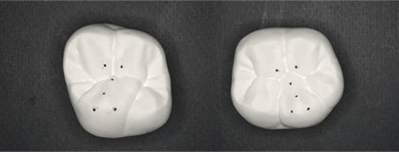

歯にはきちんと山と谷があり、点と点でしっかり咬み合うことにより顎の位置は安定します。

そこで上下の歯がしっかり咬めるように設計図を作製します。

グレーの部分は、すり減ったところを追加修正している状態です。